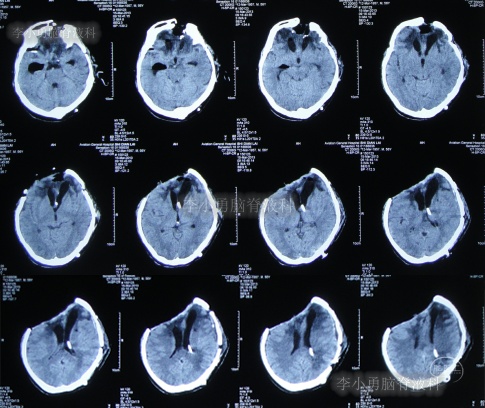

为求进一步治疗,2022年4月29日,第2次来李小勇脑脊液科治疗。入院时:意识不清,刺痛后四肢能动(图-31),查头颅CT(图-32)示脑室有扩张,有积气。

图-32:2022年4月29日头颅CT

入院后当天进行了原分流管拔除术+脑室引流术,术后当天查头颅CT示有出血(图-33)。

图-33:2022年4月29日术后头颅CT

术后5天即2022年5月3日,查头颅CT示脑室有缩小(图-35)。

图-35:2022年5月3日头颅CT

2022年5月13日(入院治疗15天),查头颅CT示脑室又有缩小(图-36)。

图-36:2022年5月13日头颅CT

2022年5月23日(入院治疗25天),查头颅CT示脑室缩小(图-37)。

图-37:2022年5月23日头颅CT

脑脊液化验变正常后于2022年9月9日(治疗133天),进行了脑室腹腔分流术(图-39)。

图-39:2022年9月9日头颅CT

2022年9月23日(李小勇脑脊液科治疗147天)出院,出院时:意识清楚,肢体活动、走路正常,住院期间脑脊液未见漏(图-40);出院前头颅CT示颅骨缺损(图-41)。

图-41:2022年9月19日出院前头颅CT